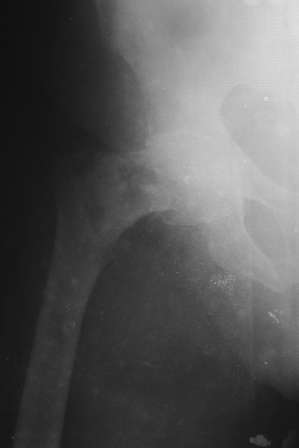

Отправлено Abdurashid Turaev 16 Январь 2008, 18:58

Доставлена больная 72 года. 3 дня назад упала. На R-грамме чрезвертельный простой АО 31А1 перелом левой бедренной кости. Кроме того имеется подозрение на субкапитальный 31В1 перелом , у меня на практике такое впервые. Трижды сделали R-графию, но качественный снимок не получилось. КТ в диагностическом центре на ремонте. 1. Действительно, имеется ли субкапитальный перелом, или мне так кажется? 2. Если да, то что можно делать? В наличии имеется длинные спонгиозные винты, большие расширяюшиеся в конце винты ЦИТО, Г- образные и продольные пластины АО, пластина Троценко-Нуждина, и мыщелковые пластины, заимствованные у Джолдаса. С уважением Абдурашид.